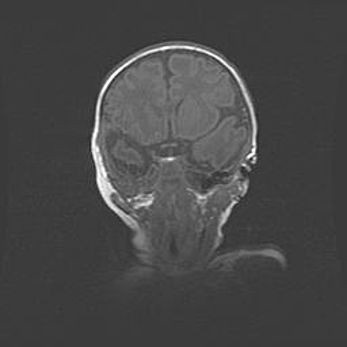

Аномалия Денди-Уокера. Признаки гипоплазии мозолистого тела.

Возраст: 5 месяцев 3 дня

Вес: 5550 г

Пол: мужской

Окружность головы: 39 см

Срок гестации: 40 недель

Аномалия Денди-Уокера – это порок развития головного мозга, для которого характерна триада симптомов: гипотрофия или аплазия червя мозжечка и/или полушарий мозжечка, расширение четвёртого желудочка с формированием ликворной кисты задней черепной ямки, гипертензионная гидроцефалия различной степени.

Гипоплазия мозолистого тела относится к дефектам внутриутробного этапа развития мозговой ткани, возникающим в процессе закладки структур головного мозга, что происходит на начальных этапах развития эмбриона.